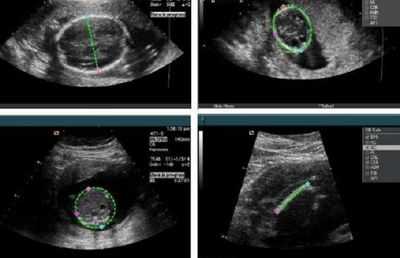

В качестве первичного метода обследования в пренатальном периоде проводится акушерское УЗИ. У новорожденных для скрининговой диагностики используется нейросонография, однако этот метод не всегда показывает хорошую информативность, особенно при парциальной агенезии. Для верификации диагноза назначаются следующие методы исследования:

- Нейросонография. При ультразвуковом сканировании головного мозга определяется крупное кистозное образование в задней части черепной коробки. На УЗИ мозжечковый червь не визуализируется, недоразвитые полушария мозжечка раздвинуты, желудочковая система мозга расширена и деформирована.

- Пренатальная диагностика. При проведении УЗИ плода удается предположить аномалию на сроке 15-16 недель, более четкая визуализация структур IV желудочка возможна после 22 недели гестации. При сочетании патологии с расщелинами лица эхосонография может быть недостаточно информативна.